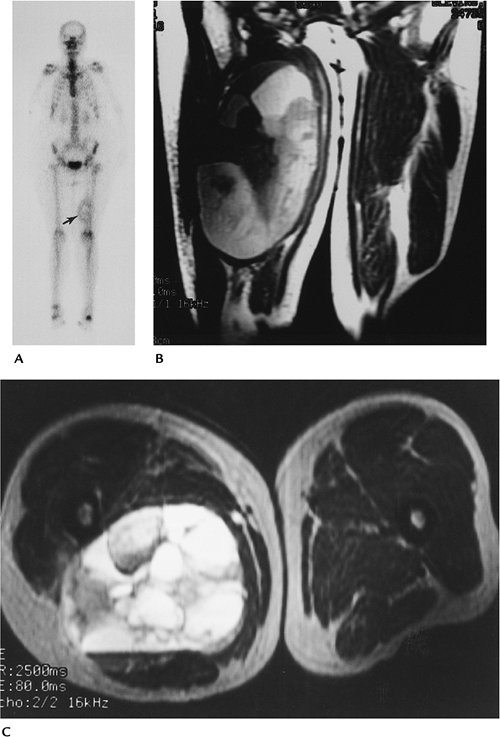

Bone Tumors/Tumorlike Conditions: Metastasis

Key Facts

-

Clinical:

Pain is the most frequent presenting symptom.

Age: adults

Sex: no sex predilection

Common locations: axial skeleton, proximal long bones

Imaging features:

Radiographic features: solitary or multiple lesions. Lesions may be lytic, sclerotic, or mixed, depending on primary tumor.

Radionuclide scans: best screening technique for most metastatic lesions. Seen as areas of increased tracer.

CT: useful for treatment planning of focal lesions

MRI: signal intensity varies:

Sclerotic, decreased signal on T1- and T2-weighted images

Lytic, decreased T1- and increased signal on T2-weighted images

Enhancement variable for lytic and

sclerotic. Diffusion or chemical shift imaging may assist in

differentiating between benign and malignant compression fractures in

the spine.

![]() |

|

FIGURE 10-37 Radionuclide bone scans of the upper (A) and lower (B) axial skeleton showing multiple foci of increased tracer caused by metastasis.

P.703

FIGURE 10-38

Sagittal T1-weighted image of the lumbar spine demonstrates a burst fracture of L1 with a large metastatic lesion in L3 extending into the posterior elements and a third lesion in L4. |